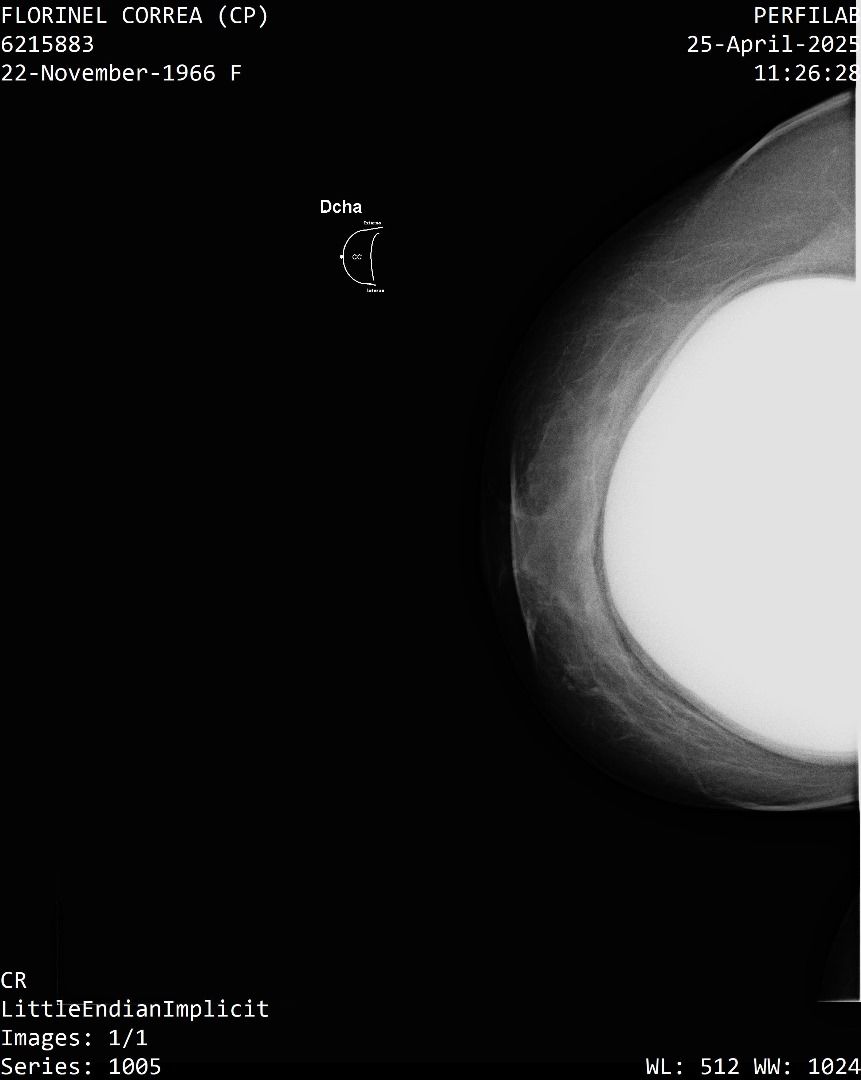

A Correa se le practicó un estudio de mamografía bilateral, la cual reporta una densidad mamaria heterogéneamente densa (ACR C), lo cual puede dificultar la detección de lesiones sospechosas.

Además, la presencia de implantes mamarios limita aún más la visibilidad del tejido mamario.

También se identificó un ganglio linfático de aspecto residual en la axila derecha que se considera sospechoso con este método, requiere evaluación urgente mediante ecografía mamaria.